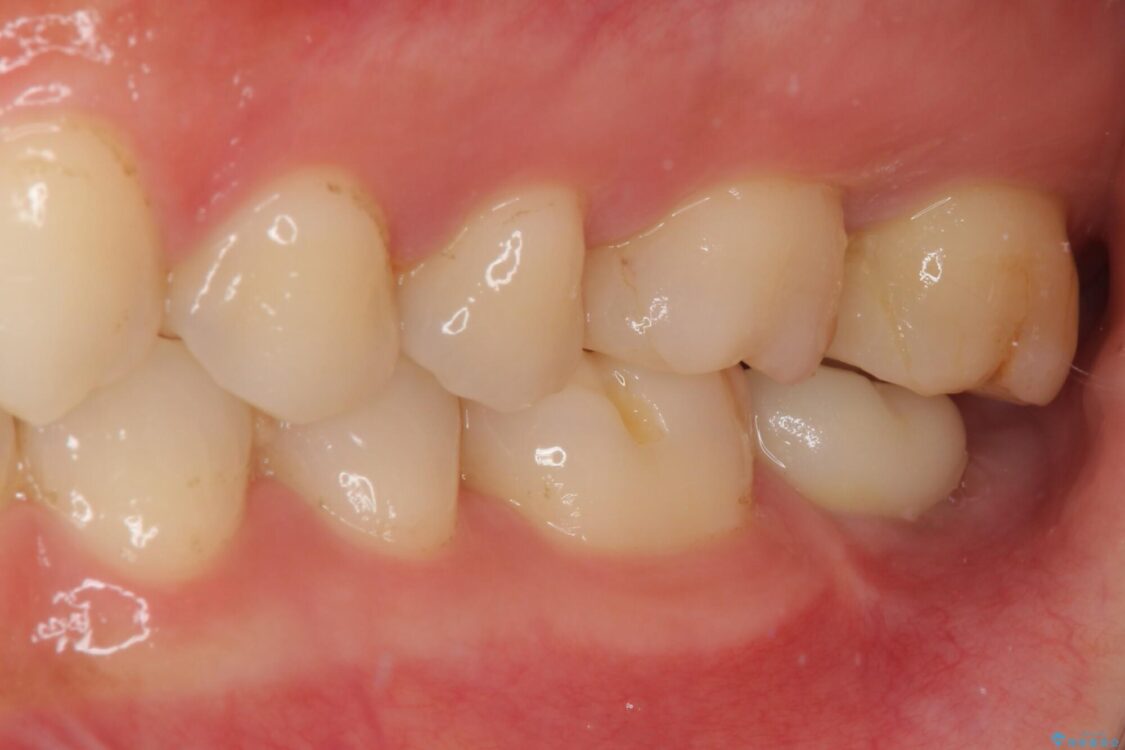

治療前

• 奥歯がズキズキと痛む 奥歯の虫歯治療 治療前画像